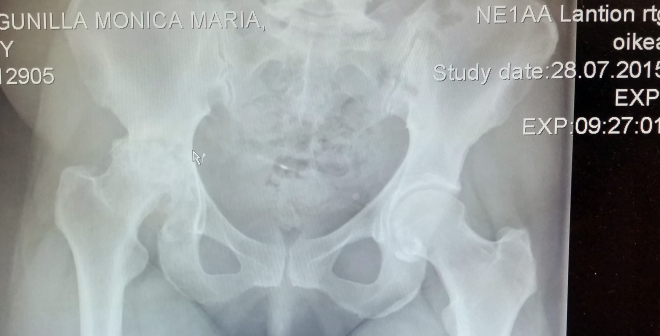

Replaced by Metal

Today I saw it

The huge chunk of metal

Replacing my joint